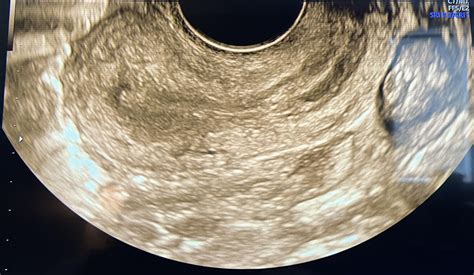

• Transvaginal Ultrasound: A specialized, slim transducer is inserted into the vagina. This method provides much clearer, more detailed images of the ovaries and uterus because the probe is closer to these organs.

• Texture and Echogenicity: The internal texture (echotexture) should appear uniform. It should not show solid masses or irregular fluid pockets that suggest pathology.

• Follicular Activity: It is entirely normal to see small, fluid-filled sacs known as follicles. These are where eggs develop. The presence of several small follicles is a sign of healthy ovarian function.

During Reproductive Years: Ovaries are active. They fluctuate in size based on the menstrual cycle. You may see a "dominant follicle" just before ovulation, which can temporarily appear larger than other follicles. This is a perfectly healthy, expected finding.